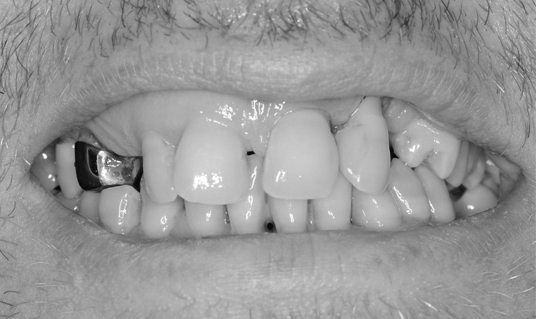

Наши работы

Верните радость улыбки

и уверенность в себе